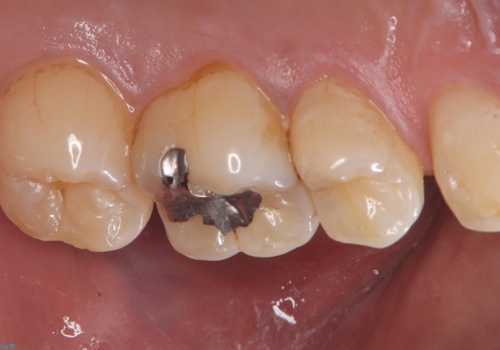

左上5番目の歯の側面に実質欠損を認め、隣の6番目の歯にも虫歯を認めたため両歯ともセラミックインレーでの治療となりました。

左上5番遠心に実質欠損を認め、さらに5番と6番の隣接面にもカリエスを認めました。6番の咬合面には、元々コンポジットレジン修復が施されており、劣化がみられたのでその部分も含め修復することとなりました。